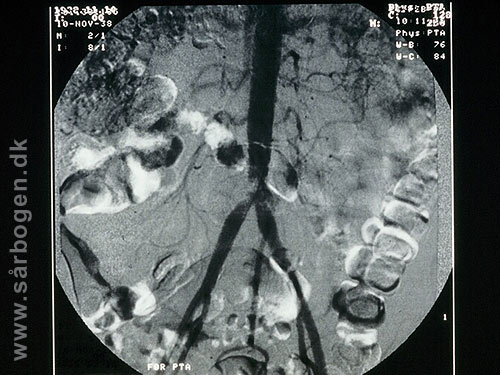

Før PTA af iliacakar...

Under PTA af iliacak...

Efter PTA af iliacak...